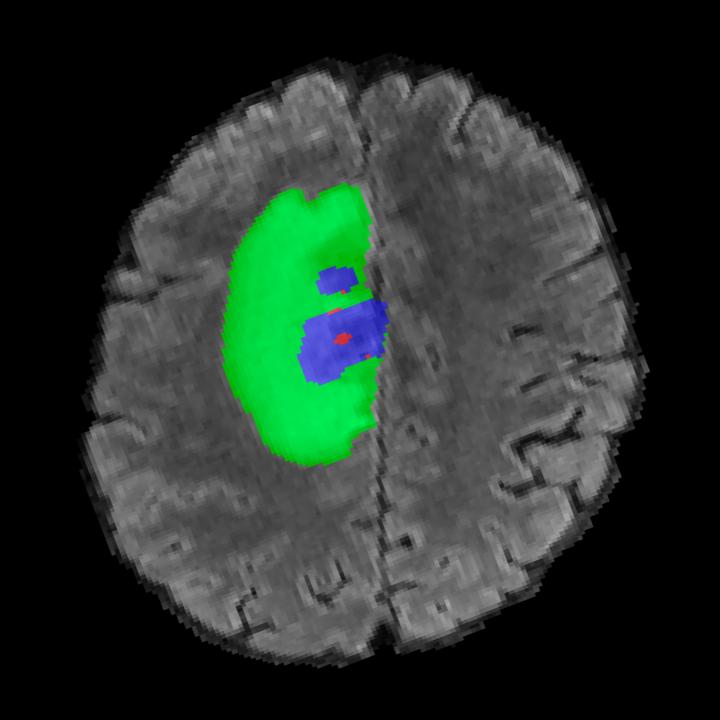

Tumour Information Preservation. For the brain tumor segmentation, we use a Swin UNETR model[27, 70], trained with random rotation, and intensity as data augmentation. In Figure 5, we highlight the tumor profiles of the generated MRIs compared to the ground truth tumour profile. In the test set with human ground-truth annotations (), the real MRI Dice score is 85.15 while the generated MRIs from a single slice have a dice score of 83.09. This shows how the generated MRIs indeed preserve the tumor information and can act as an affordable and informative pseudo-MRI, before conducting an actual costly MRI examination in hospitals.

B.4 Tumour Information Preservation

On the test set with human ground-truth annotations (), the brain volumes generated from single slice input preserve the volume of the different tumour components (paired t-test, for all 3 classes) (see Table 3). The real MRI Dice scores are put for reference to our generated MRIs. X-Diffusion outperforms baselines TPDM [36] and ScoreMRI [18] in tumour preservation (see Table 3 and Figure 12). We ran experiments comparing the tumour segmentation Dice Score varying X-Diffusion configurations. The multi-slice input X-Diffusion achieves a marginally better Dice Score than the single-slice input model (83.47 83.09). We also ran experiments with slice input used for volume reconstruction intersecting or not with tumour. We observe on average a drop of 6% Dice Score (see Table 3). Further away from the tumour the input slice for volume reconstruction is selected, and we observe a linear decrease in tumour segmentation Dice Score with the lowest value of 77.21 Dice Score (see Figure 15).

This shows how the generated MRIs indeed preserve the tumour information and can act as an affordable and informative pseudo-MRI, before conducting an actual costly MRI examination in hospitals. Given that our model has been trained on brain scans all with tumours, we expect to see hallucinations of tumours in healthy scans. We report two cases of failure of our model in Figure 16. Hallucinations of tumours on healthy samples represent 2% of the test set.